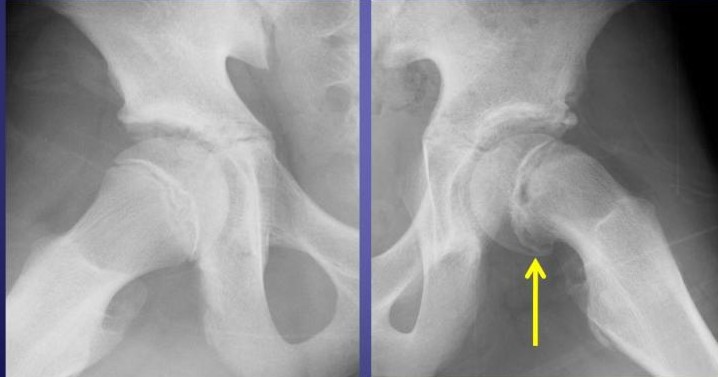

整形外科ではまず、レントゲン検査を行い、

大腿骨頭(だいたいこっとう)がどの程度ずれているかを確認します。